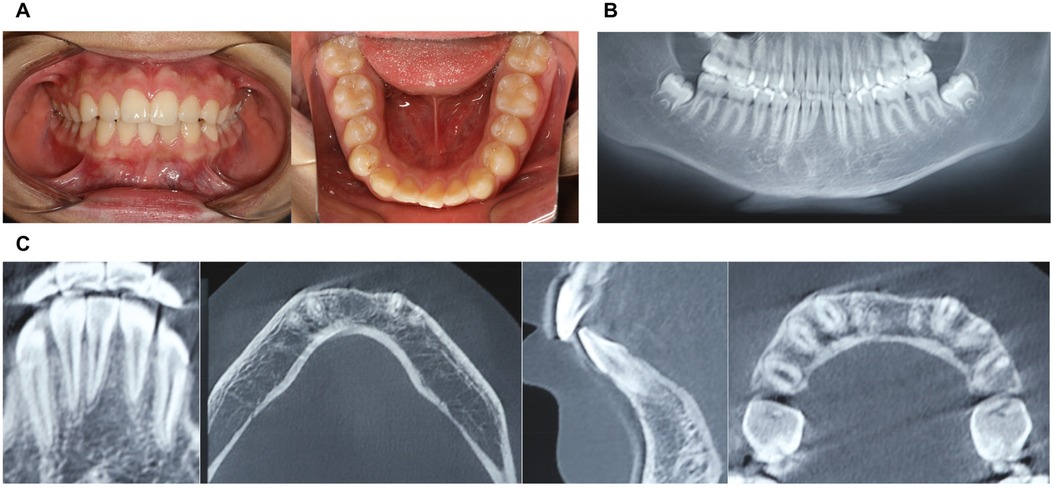

The patient returned for a postoperative review two weeks after surgery, with the surgical site showing good healing and no reported discomfort (Figures 4A,B; Figures 5A–C).

Figure 5. Physical and CBCT examination one year after surgery. (A) Photos of intraoral view; (B) CBCT examination (overall view); (C) CBCT examination.